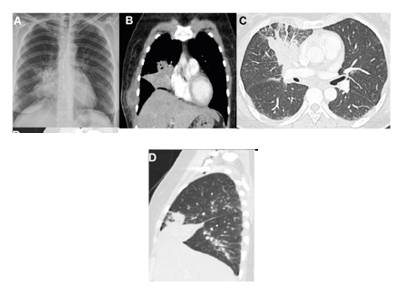

Inicialmente, se la trató en el servicio ambulatorio en un centro de atención primaria en donde se le tomó una radiografía simple de tórax que evidenció una consolidación incipiente en el lóbulo medio; fue tratada en casa durante siete días por vía oral con 750 mg de sultamicilina cada 12 horas y 500 mg de claritromicina cada 12 horas.

A pesar de la mejoría inicial (disminución de la tos y de la fiebre), la paciente volvió a consultar por presentar dolor en el hemitórax derecho y sensación de masa en la piel a nivel del sexto arco costal derecho. En el examen físico, se evidenció en la piel una formación sugestiva de absceso (eritematosa, bordes mal definidos, induración a la palpación, de 4 x 3 cm, aproximadamente) (figura 1), de la cual se obtuvo una muestra para cultivo, el cual fue negativo a los siete días de incubación.

Se descartaron: infección por HIV (ELISA de cuarta generación con resultado no reactivo); tuberculosis (baciloscopias seriadas en tres momentos diferentes, todas negativas, así como cultivos para micobacterias en medio líquido a partir de muestras de esputo, lavado broncoalveolar y piel, con resultados negativos); neoplasias gastrointestinales y abdominales (esofagogastroduodenoscopia y colonoscopia con biopsias negativas para malignidad y atipia celular, tomografías con contraste de tórax y abdomen en las que se evidenció disminución significativa de la consolidación pulmonar, resolución de la lesión en tejidos blandos y la piel del hemitórax derecho sin otros hallazgos relevantes); infección por virus linfotrópicos (pruebas de IgM e IgG no reactivas para citomegalovirus y virus de Epstein-Barr), y hepatotrópicos (pruebas no reactivas de anticuerpos para virus de hepatitis C, antígeno de superficie de hepatitis B, anticuerpos para antígeno de superficie de hepatitis B, anticuerpos anti-core totales de hepatitis B y anticuerpos IgM para hepatitis A). Se practicaron una fibrobroncoscopia y un lavado broncoalveolar en el que se registró un conteo elevado de neutrófilos (18 %) con cultivo negativo para hongos, bacterias y micobacterias, en tanto que la citometría de flujo del líquido cefalorraquídeo no arrojó resultados sugestivos de un proceso infeccioso o neoplásico.